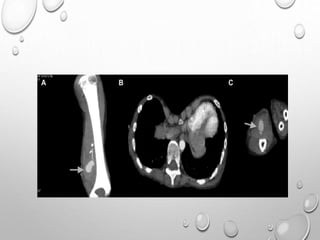

CORONAL COMPUTED TOMOGRAPHY SCAN OF THE ANKLE

DEMONSTRATING IRREGULARLY SHAPED PROTUBERANT BONE

(WHITE ARROW) IN THE MEDIAL ASPECT OF THE JOINT (A). AXIAL

COMPUTED TOMOGRAPHY SCAN OF THE ANKLE DEMONSTRATING

AN IRREGULARLY SHAPED PROTUBERANT BONE LESION OF THE

MEDIAL ANKLE JOINT, WITH A PORTION CONNECTED TO THE

ANTERIOR TALUS, AND A SECOND LESION MORE POSTERIORLY

LOCATED AND A DEFINED CLEFT (BLACK ARROWS) AT THE

INTERFACE (B).